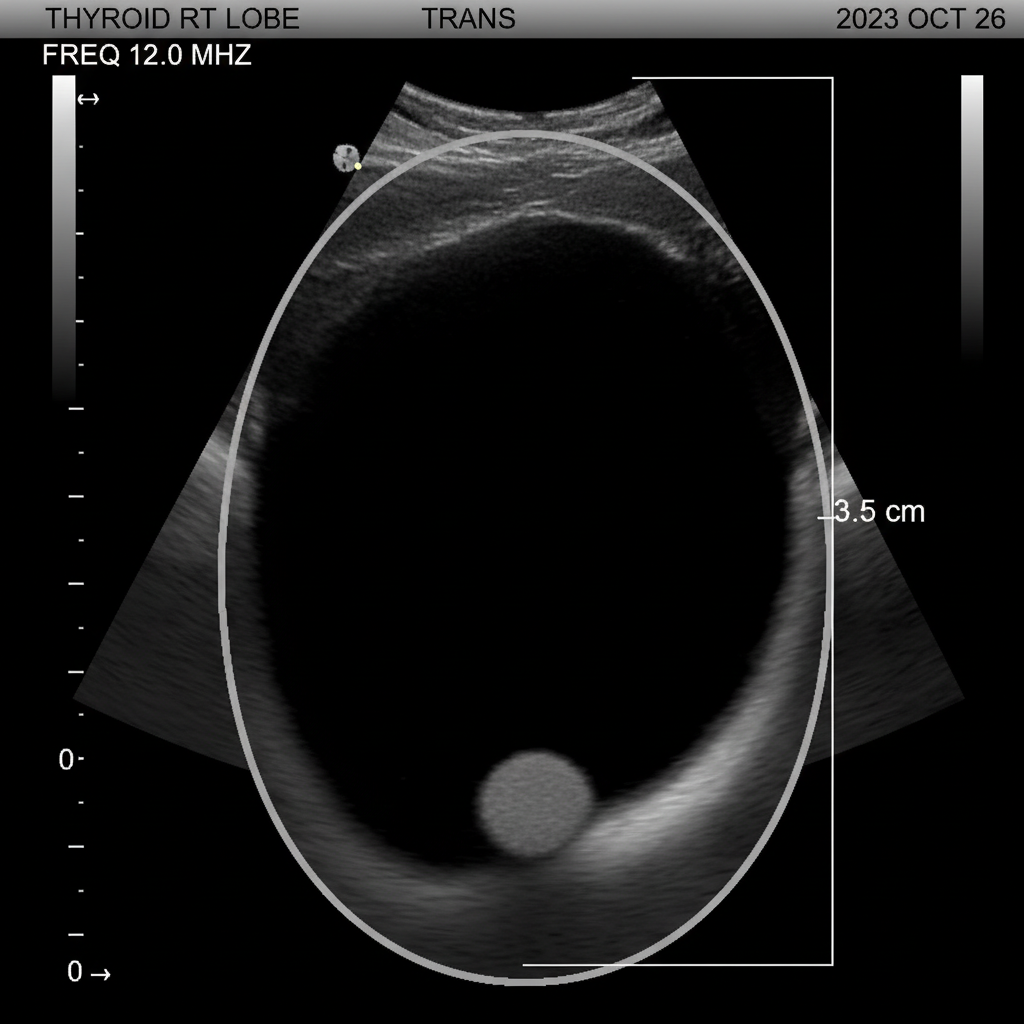

- 갑상선 초음파: 갑상선 내부의 결절 유무, 크기, 모양, 경계 등을 아주 자세히 확인할 수 있는 검사예요.비교적 간단하고 통증 없이 진행돼서 많이 사용된답니다.암이 의심되는 결절이 발견되면 다음 단계로 넘어가죠.